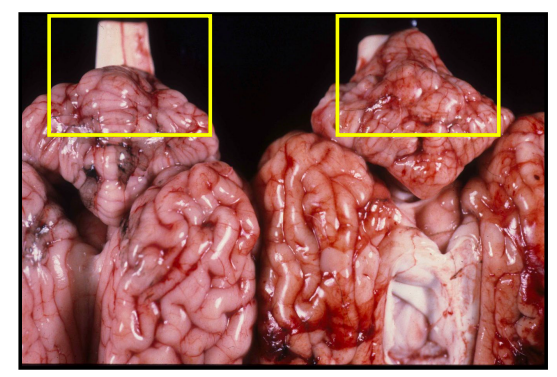

Nota visual:

Imagen de pleuritis fibrinosa y fibrosa; en la primera la fibrina se desprende fácilmente.

Neumonía fibrinosa

Características:

- Aumento de tamaño de la zona afectada.

- Pulmón duro, marmóreo (vetas de color).

- Exudado fibrinoso en alvéolos, bronquios y linfáticos dilatados.

Fases:

- Congestión y edema: color rojo vivo, flujo sanguíneo abundante.

- Hepatización roja: color oscuro, consistencia firme, fibrina en alvéolos.

- Hepatización gris: color gris-rojizo, predominan leucocitos.

- Lisis y resolución: exudado reabsorbido o expectorado.

Curación: reabsorción o fibrosis cicatricial.

Ejemplo visual:

Pericarditis y pleuritis fibrosa con adherencias; “sinequias” visibles.